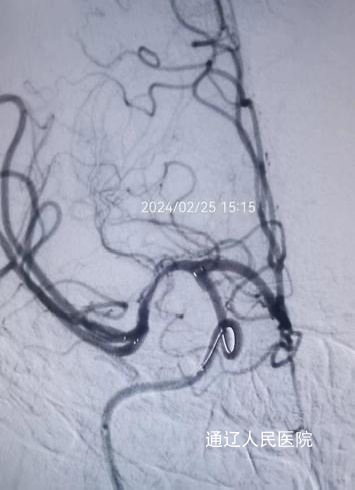

年纪这么小,为什么会出现偏瘫?卒中中心值班医师刘美玉心中充满了疑问,经过详细地询问病史及体格检查,结合头颅CT结果,并与上级医师沟通后,刘美玉医师给出了初步诊断——急性缺血性脑血管病。医师与家属充分沟通并取得其同意后,立刻给予静脉溶栓治疗,为患者争取血管再通的机会。因患者神经功能缺损较严重,介入组医师会诊后,做进一步脑血管造影检查,结果提示患者右侧大脑中动脉闭塞,为责任血管。西院神经外科张永哲主任,神经内一科张建辉主任为其进行脑动脉溶栓、动脉取栓、球囊扩张及支架置入术,手术历时3个小时,过程虽波折,但结局很好,实现了闭塞动脉的再通。

术后